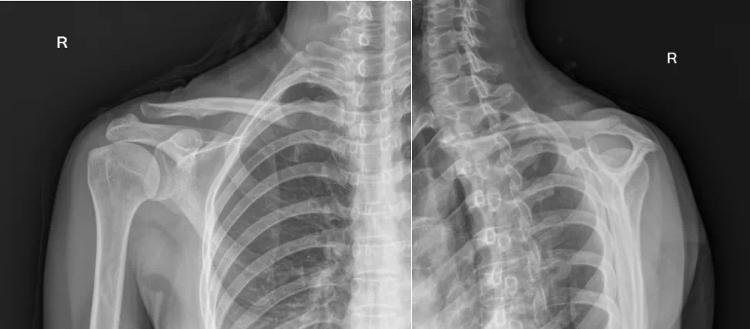

右肩关节正位+Y位 X线:可见肱骨大结节增生,以及二型肩峰